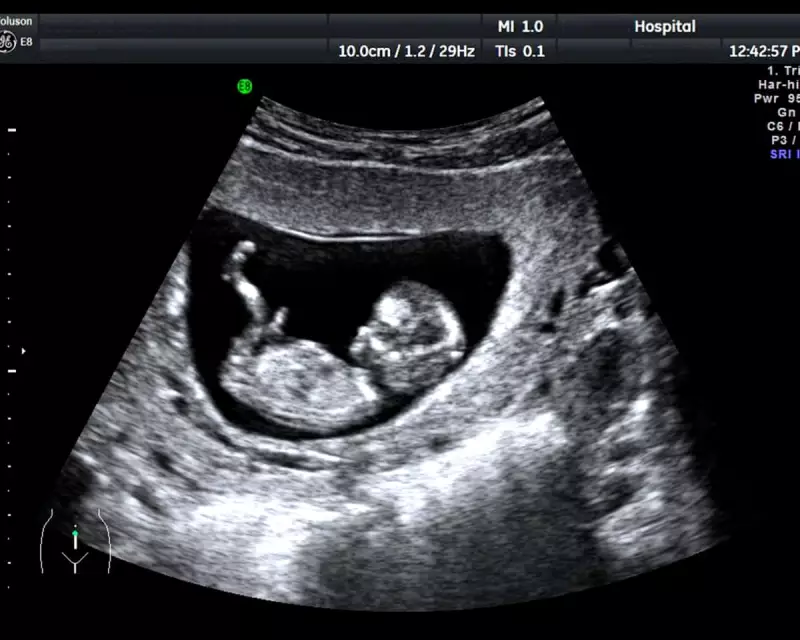

Britain is facing a growing healthcare crisis as unregulated private pregnancy scan clinics operate without proper oversight, putting both mothers and babies in potential danger, leading medical experts have warned.

Across the UK, numerous private clinics offering pregnancy ultrasound scans are functioning without mandatory regulation, creating what experts describe as a "postcode lottery" of safety standards. These facilities can operate without trained sonographers, proper equipment maintenance, or established procedures for detecting serious health issues.